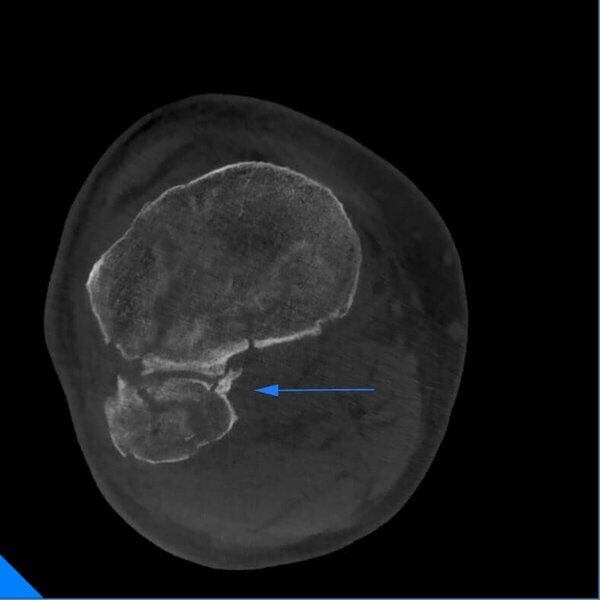

Frattura multipla ginocchio